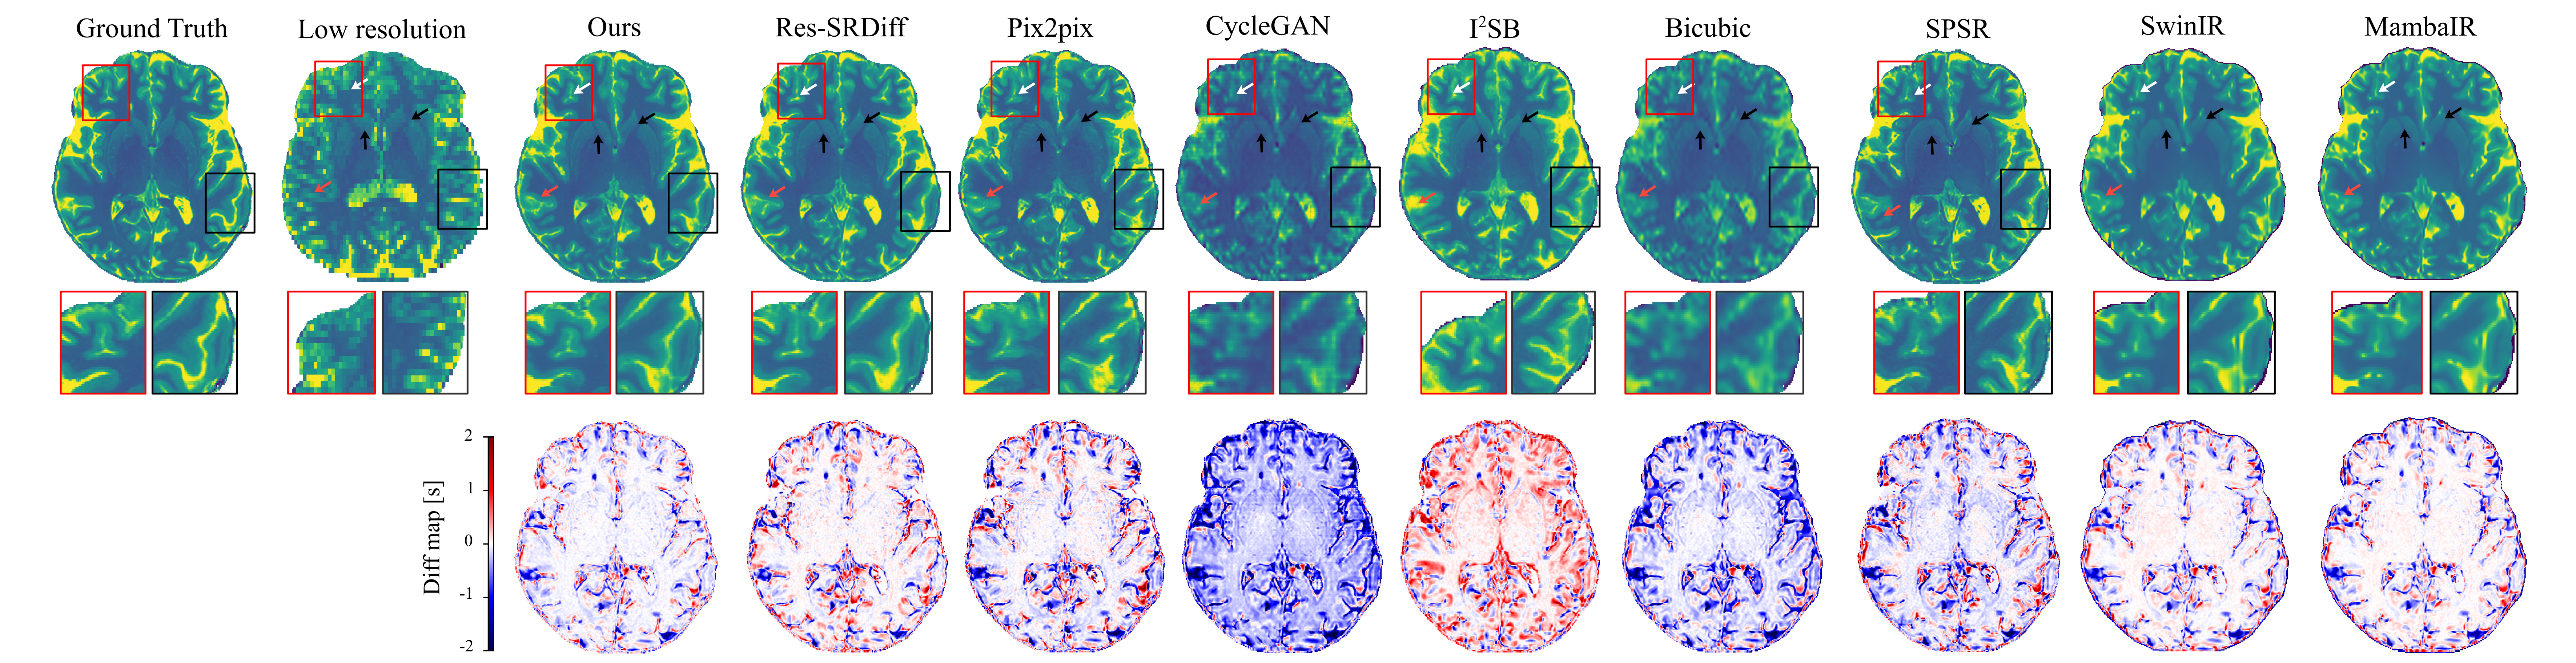

Figure 3 shows qualitative comparisons of super-resolution results on 7T brain T1 MP2RAGE maps. The first row displays reconstructed images, while the second row depicts difference maps relative to the ground-truth HR image. The proposed method yields the most faithful reconstruction of fine anatomical details. Subtle cortical and subcortical structures (white arrows) are more sharply delineated, and the head of the caudate nucleus and putamen (black arrows) are more accurately recovered compared to competing approaches. Both our model and Res-SRDiff demonstrate improved recovery of these regions, whereas Bicubic and CycleGAN produce pronounced blurring and loss of structural definition. Pix2pix and SPSR achieve moderate improvements but still fail to preserve fine tissue boundaries. SwinIR shows reasonable global consistency but exhibits residual blurring in cortical ribbon regions, while MambaIR captures local edge details but introduces minor inconsistencies in subcortical structures. The difference maps further support these observations: our method yields the lowest overall error relative to the ground truth, followed closely by Res-SRDiff. In contrast, Bicubic, CycleGAN, SwinIR, and MambaIR exhibit higher residual variations, reflecting suboptimal structural fidelity. Collectively, these qualitative results highlight the capability of our approach to preserve anatomically relevant features while minimizing reconstruction artifacts.

Figure 3: Qualitative comparison of super-resolution methods on 7T brain T1 MP2RAGE maps. The first row shows reconstructed images, the second row is the zoomed-in regions, and the last row depicts difference maps with respect to the ground-truth HR image. Arrows highlight cortical and subcortical structures (white: cortical ribbon; black: caudate nucleus and putamen; red: subtle tissue boundaries).

Quantitative evaluation across four image quality metrics (SSIM, PSNR, LPIPS, and GMSD) further demonstrates the superiority of the proposed method (Table 1, Figure 4). Our model achieved the highest mean SSIM score (0.951±0.0210.951\pm 0.021), surpassing all competing techniques, with SPSR ranking second (0.932±0.0250.932\pm 0.025). For PSNR, our model reached 26.900±1.41026.900\pm 1.410 dB, outperforming Res-SRDiff (26.282±1.41826.282\pm 1.418 dB) and substantially exceeding Pix2pix, SPSR (\sim24.7 dB), SwinIR (24.022±1.61524.022\pm 1.615 dB), and MambaIR (25.309±1.08625.309\pm 1.086 dB). In terms of perceptual similarity (LPIPS), our method obtained the lowest score (0.076±0.0220.076\pm 0.022), indicating superior perceptual fidelity compared with SPSR (0.078±0.0210.078\pm 0.021), Res-SRDiff (0.083±0.0240.083\pm 0.024), SwinIR (0.229±0.0790.229\pm 0.079), and MambaIR (0.188±0.0710.188\pm 0.071). Finally, for distortion sensitivity (GMSD), our approach again delivered the best value (0.083±0.0170.083\pm 0.017), outperforming Res-SRDiff (0.086±0.0170.086\pm 0.017), SwinIR (0.117±0.0220.117\pm 0.022), MambaIR (0.110±0.0190.110\pm 0.019), and all other baselines.

Statistical testing confirmed the robustness of these findings. The Kruskal-Wallis omnibus test revealed significant group differences for all four metrics (SSIM: p<0.001p<0.001; PSNR: p<0.001p<0.001; LPIPS: p<0.001p<0.001; GMSD: p<0.001p<0.001). Post-hoc Dunn tests with Holm-adjusted pp-values showed that our method significantly outperformed nearly all baselines across all metrics (adjusted p<0.001p<0.001 in most pairwise comparisons). These results confirm that the proposed framework consistently achieves statistically significant improvements in both fidelity- and perceptual-based metrics, establishing its robustness compared to the baseline models.

Importantly, these gains were achieved with substantially improved computational efficiency. Our model requires only 0.9M parameters and 57 GFLOPs, compared with Res-SRDiff (394M parameters, 2316 GFLOPs), SPSR (96M parameters, 871 GFLOPs), SwinIR (2M parameters, 369 GFLOPs), and MambaIR (1M parameters, 113 GFLOPs). This exceptional reduction highlights the favorable trade-off between accuracy and computational cost, making the method highly suitable for scalable clinical integration. Results are reported with two decimal places in tables for readability and three decimals in the text to emphasize fine-grained differences.